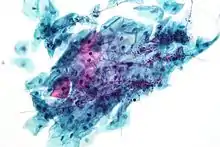

Endocervical adenocarcinoma on a pap test.